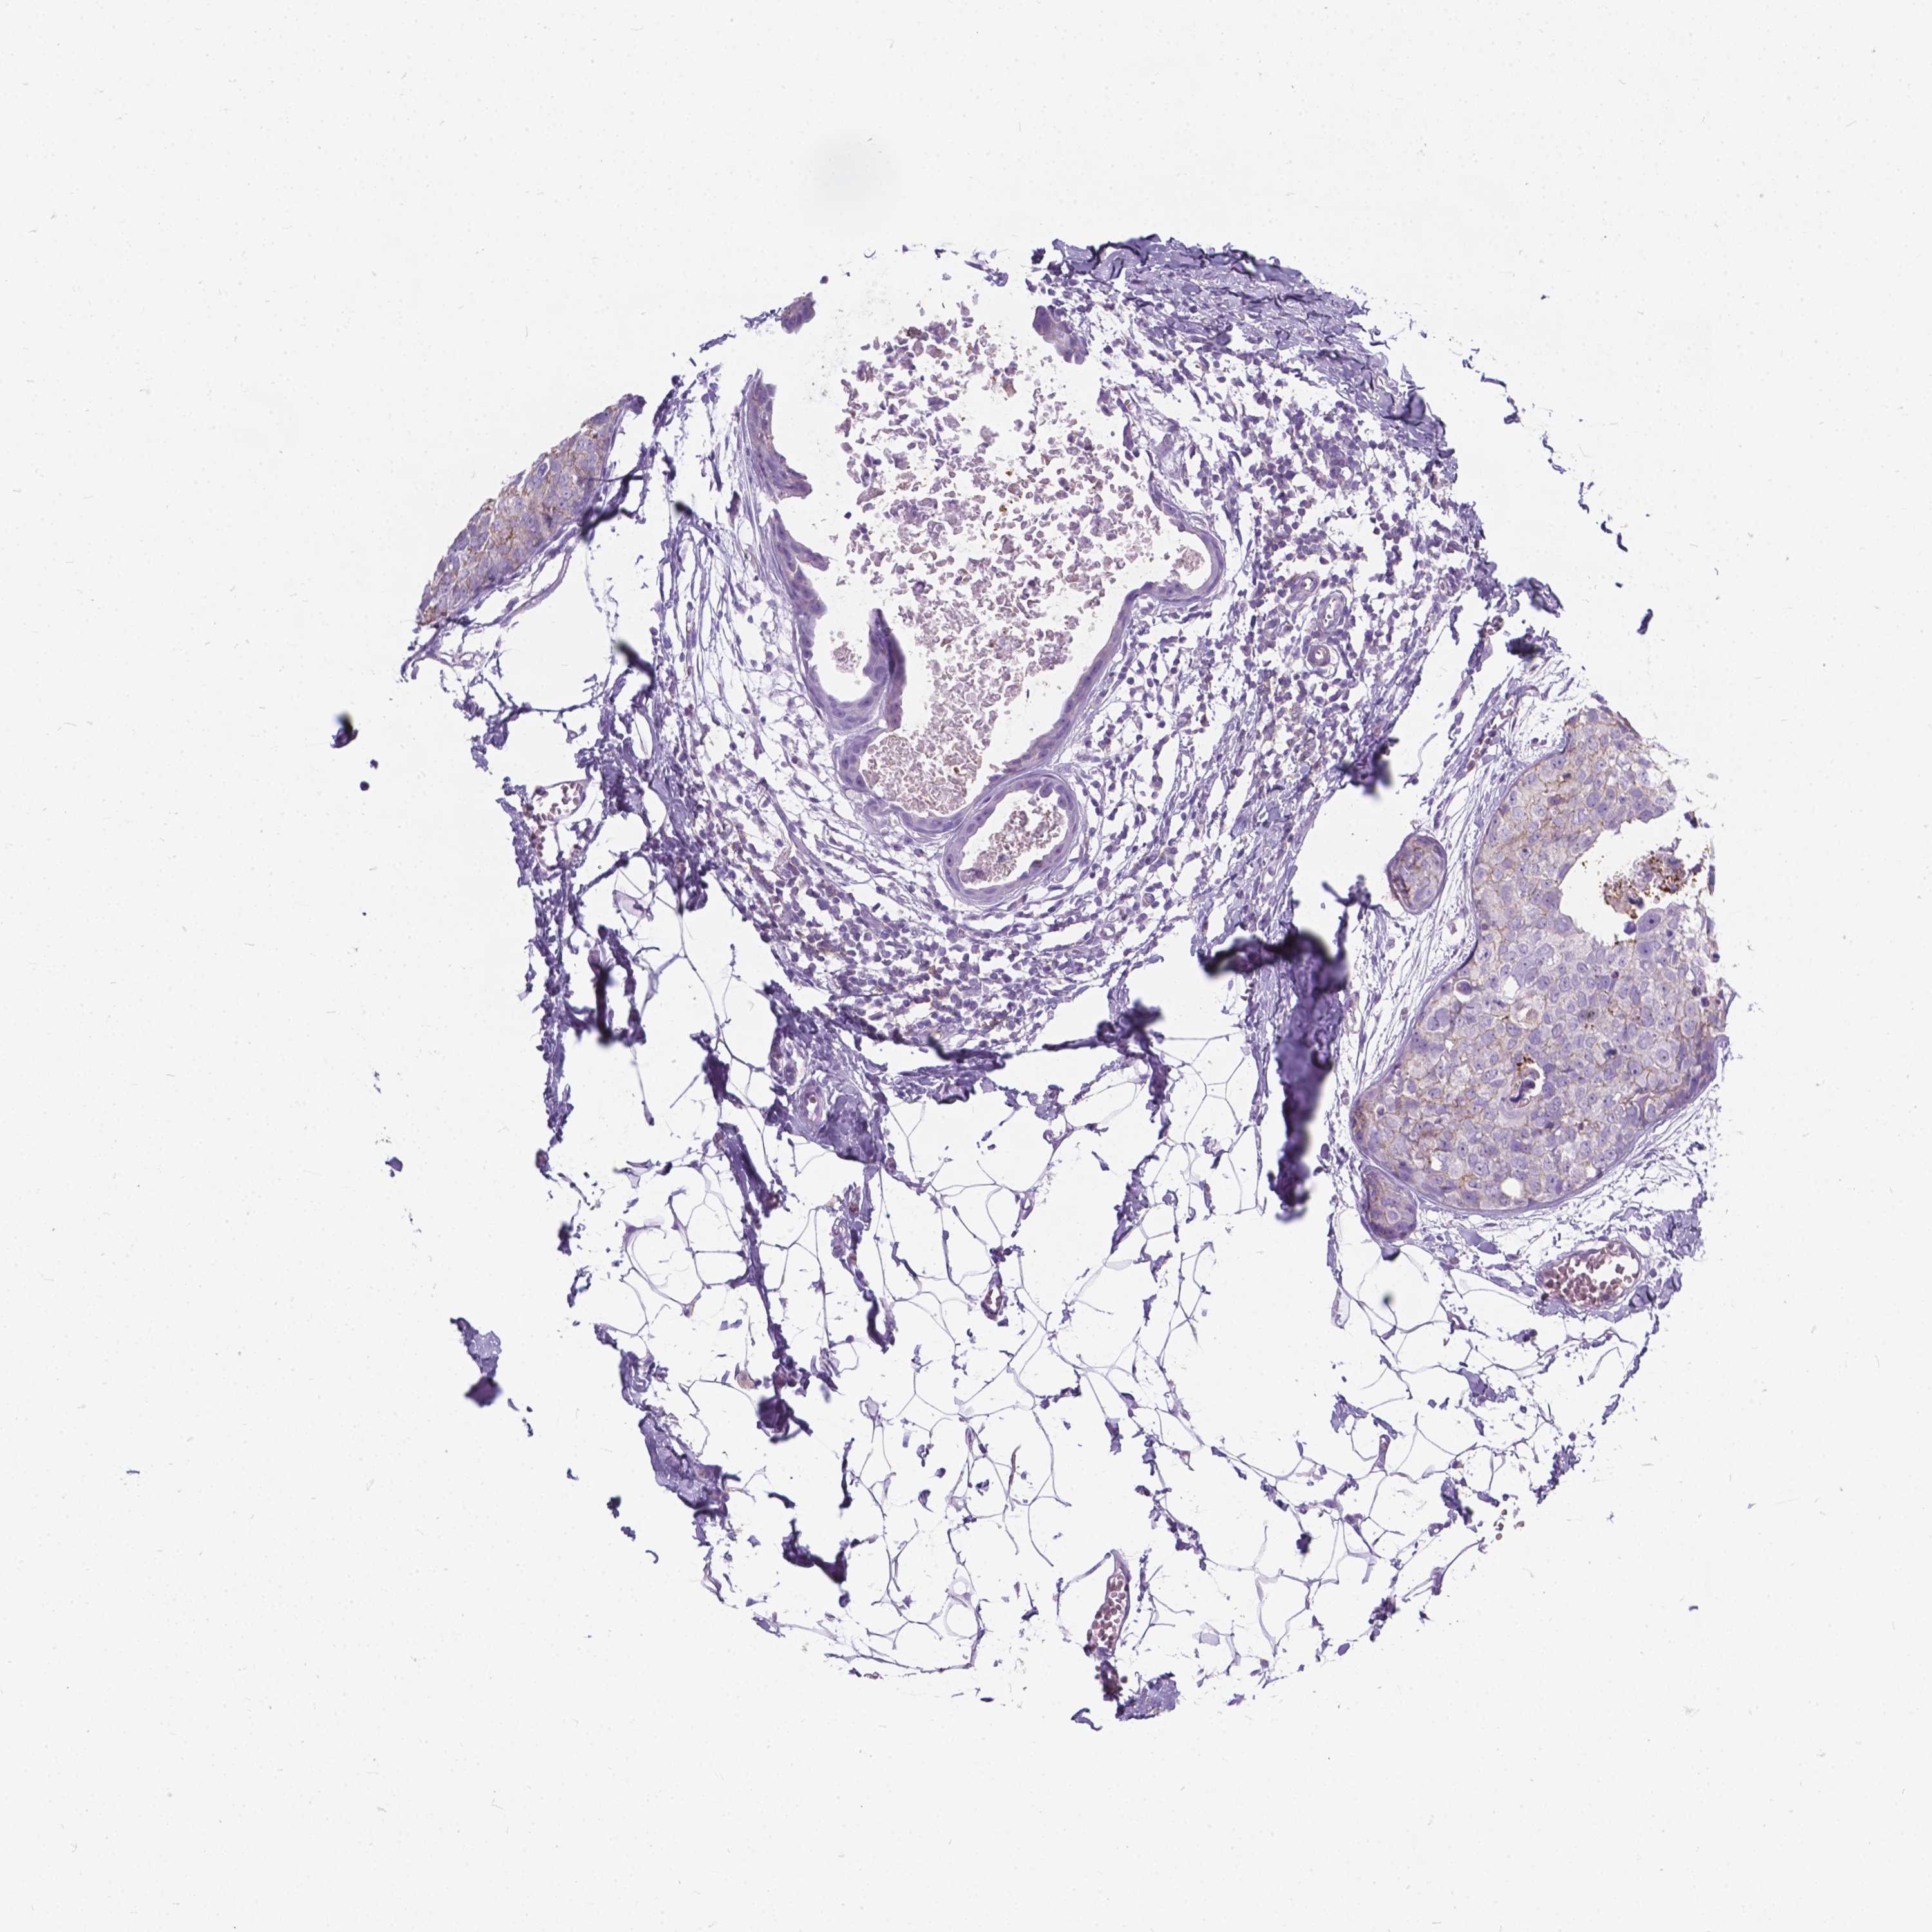

BRCA TCGA BRCA VALIDATION PROTEIN EXPRESSION

ANTIBODIES

AND

VALIDATION